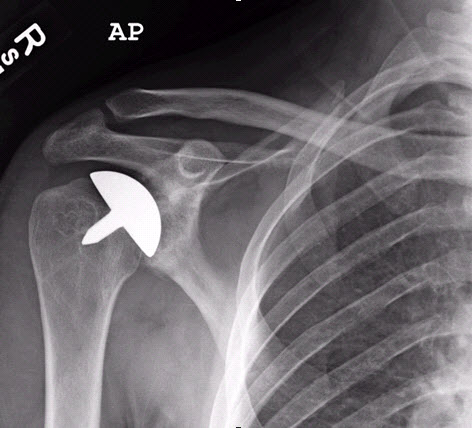

• Röntgenbilder (Nachweis einer Gelenkspaltverschmälerung, Nachweis von knöchernen Anbauten, exakte Beurteilung des Pfannenverschleißes)

• Die "klassische" Schultergelenkstotalprothese